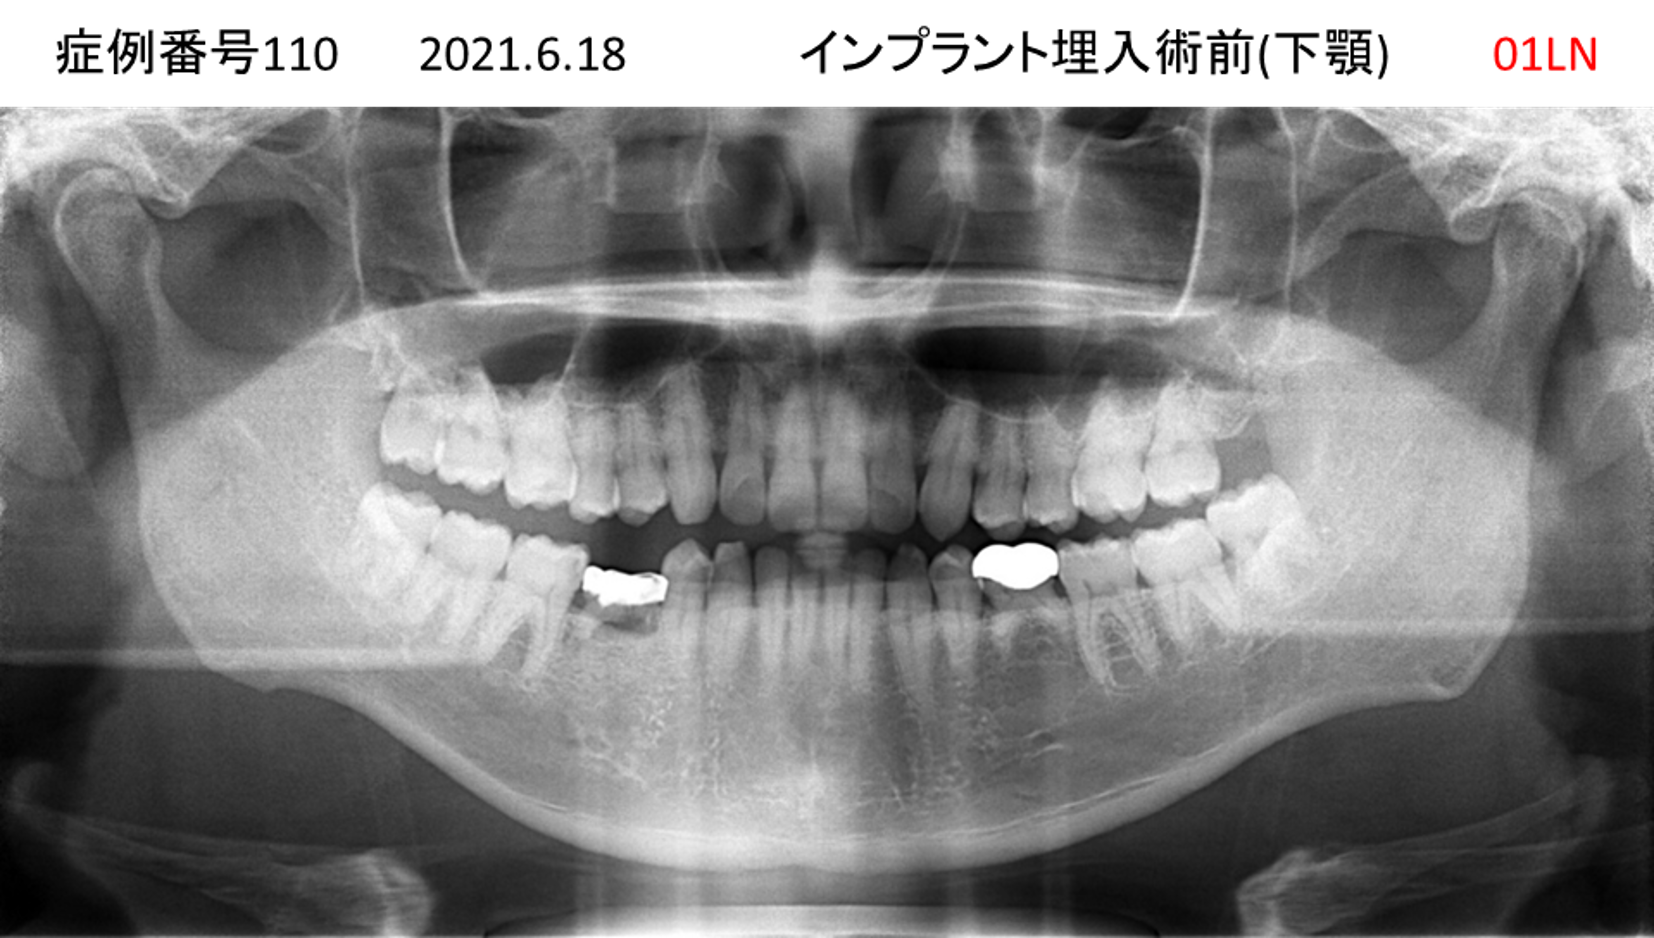

奥歯で噛めない患者様のインプラント症例

| 治療名称 |

インプラント |

| 治療費用 |

200万円+税 |

| 治療期間 |

4か月 |

| 患者さんの症状(主訴) |

奥歯で噛めない。 |

| 治療内容 |

| 治療結果 |

固いものもしっかり噛める。見た目がとても良くなった。 |

| 治療の注意点(リスク/副作用) |

インプラントが壊れたら再治療が必要 |